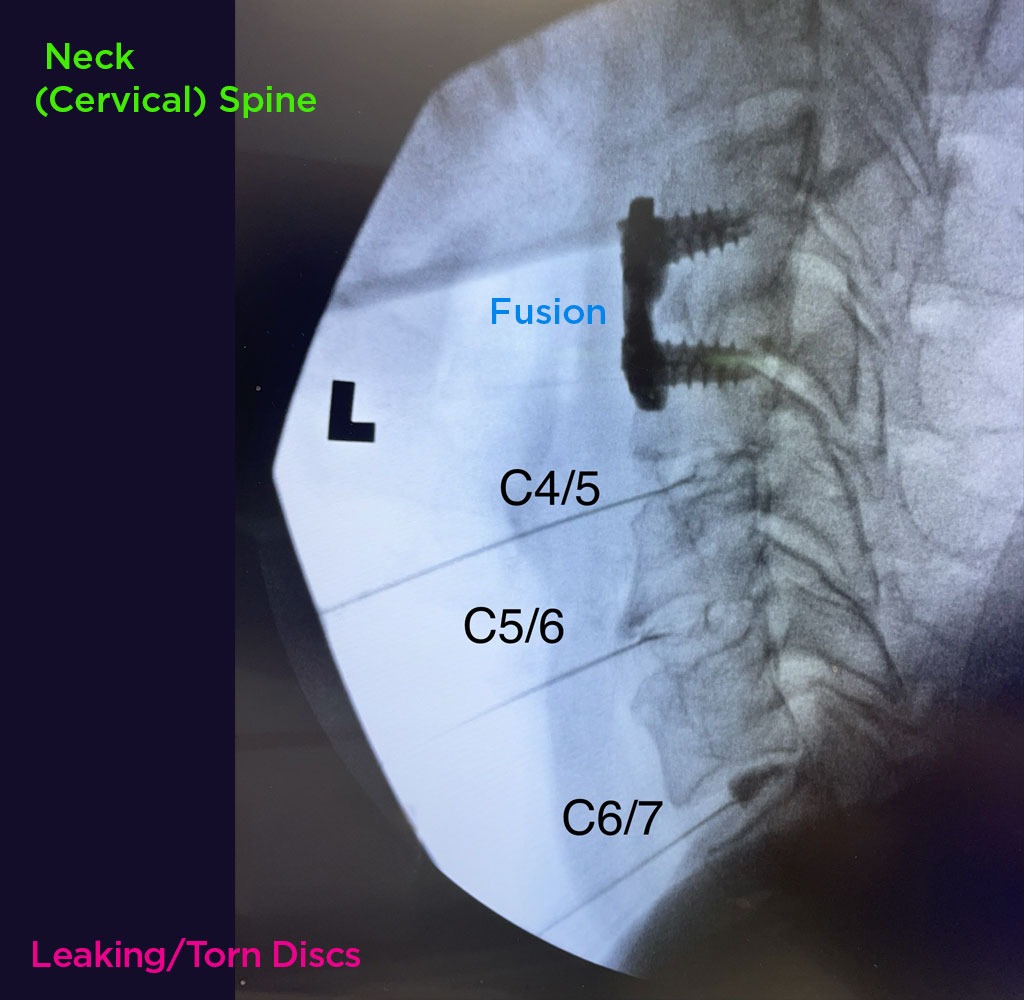

Annulargram™ Gallery

This gallery contains Annulargram images.

The Annulargram is a pain-free test and a crucial part of the DISCSEEL Procedure that identifies even the most subtle tears in spinal discs that MRI and discography cannot.

During the Annulargram, every disc in the region is tested to address current and future pain issues by finding even the most subtle annular tears. With the Annulargram, damaged spinal discs are pinpointed and precisely treated with Fibrin, leaving all healthy discs as they are.